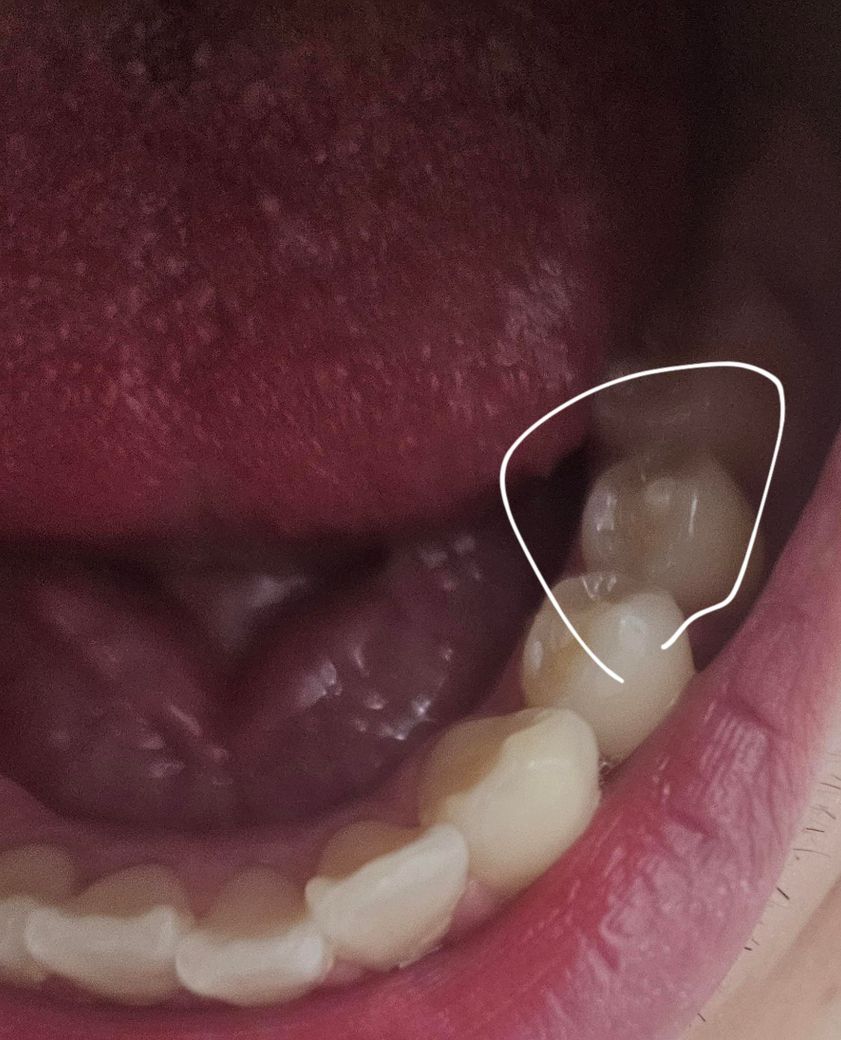

25살 입니다 치외치가 있는데 치료를 안해주는데 왜 그런건가여?

오늘 처음으로 치외치를 발견하고 갔습니다. 25살이라 그런지 약간 자연 마모가 되어있었습니다. 그런데 발견하고 인터넷에서는 가면 레진이나 갈아서 치료를 해준다는데 왜 치료를 안해주는 걸까여?

아래 작은 어금니 뒷쪽 두개에 났습니다.

• 1번 째 사진